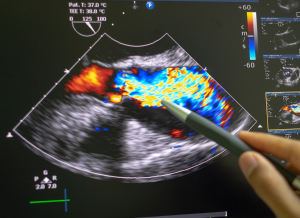

En esta sección, encontrarás una selección de exámenes recomendados para el chequeo preventivo de adolescentes y niños. Un chequeo general completo puede detectar una amplia gama de condiciones que afectan a los más jóvenes, como: Anemia, Infecciones, Problemas hepáticos, Colesterol y triglicéridos alterados, Diabetes o resistencia a la insulina, Problemas renales, Desequilibrios electrolíticos, Alteraciones de la tiroides y Arritmias cardíacas.